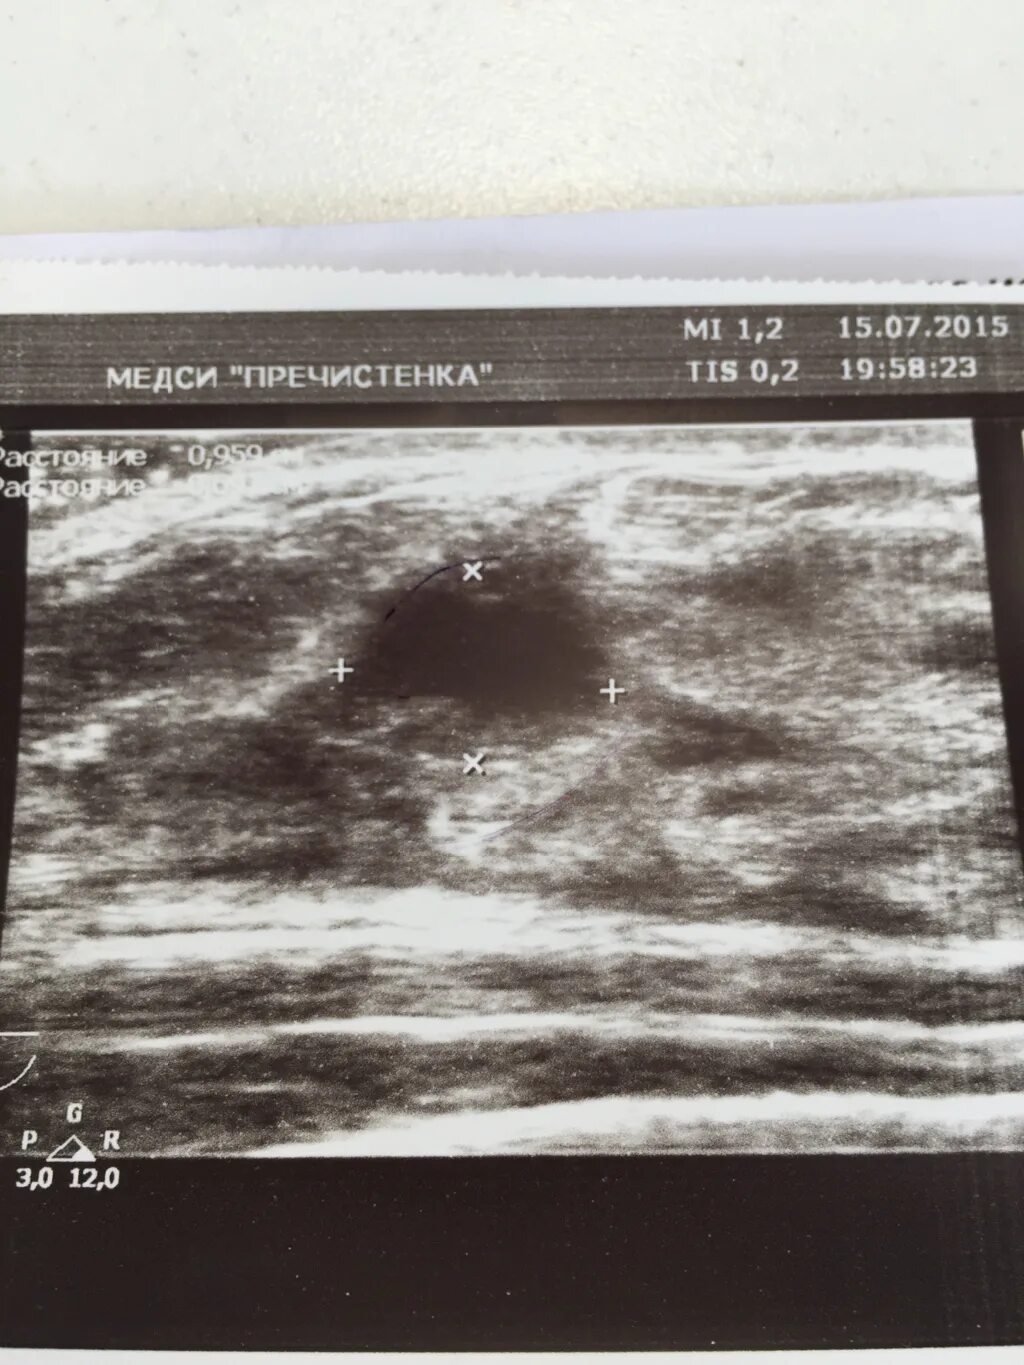

Узи молочных киров